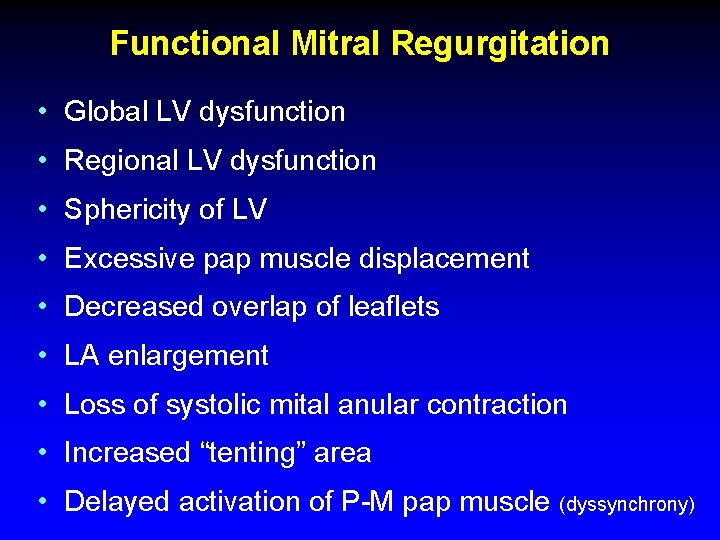

Functional Mitral Regurgitation • Global LV dysfunction • Regional LV dysfunction • Sphericity of LV • Excessive pap muscle displacement • Decreased overlap of leaflets • LA enlargement • Loss of systolic mital anular contraction • Increased “tenting” area • Delayed activation of P-M pap muscle (dyssynchrony)